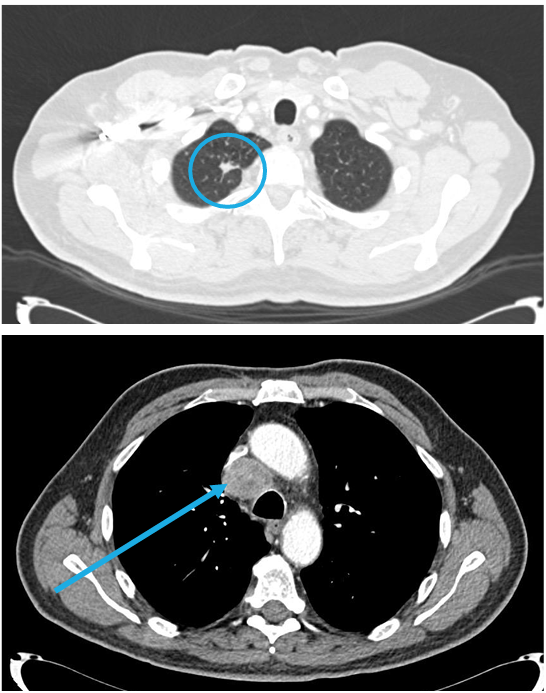

65岁男性,既往重度吸烟史(50包/年),ECOG PS 1分。因肩胛区疼痛入院治疗。胸部CT显示,右肺上叶可见一巨大肿块,最大径达7.3cm。病灶疑似侵犯椎体及胸膜,并伴有可疑的4R组淋巴结肿大。PET/CT显示,原发病灶SUV最高值为17,4R组淋巴结SUV最高值为11。MRI未见转移。临床分期定为cT4N2M0(IIIB期)。

针对此类高负荷T4且伴有N2淋巴结受累的病灶,治疗决策存在明显分歧:

倾向内科治疗/放疗:鉴于T4病灶巨大且伴有N2,根治性同步放化疗后接度伐利尤单抗是目前的标准治疗。

挑战外科治疗:对于部分潜在可切除的T4,通过新辅助免疫联合化疗,若能实现降期且达到R0切除,可能为患者带来更持久的生存获益。